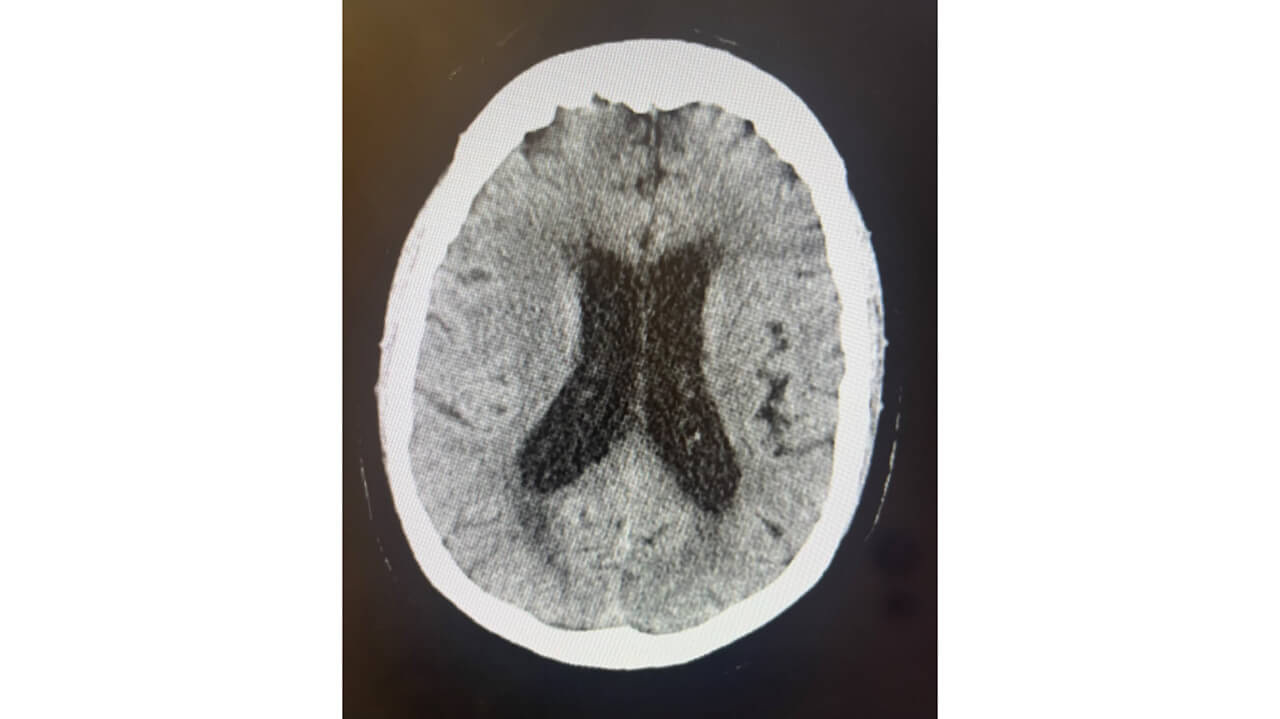

CT head w/o contrast 10/13 10pm